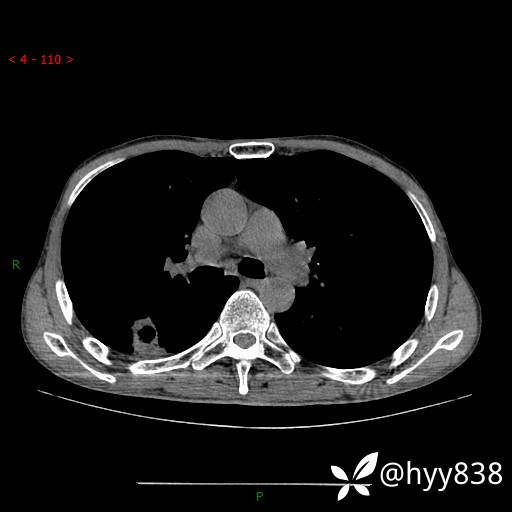

老年男性,肺团片状占位+体重下降,肿瘤 VS 真菌 VS 细菌,看看你的意见--结果公布~

简要病史:患者7天前无明显诱因出现咳嗽咳痰,咳绿色、褐色痰,吸烟后加重,伴心慌、胸闷,无畏寒发热,无头晕头痛,无鼻塞流涕,无痰中带血及咯血,无胸痛、呼吸困难,无全身酸痛,为求进一步诊治于我院就诊,门诊完善胸部CT提示“右下肺团片状影,考虑肿瘤?感染?”,门诊以“咳嗽待查”收住入院。 起病以来,患者精神、饮食、睡眠尚可,大、小便正常,体力下降,体重下降8斤。空腹血糖:6.42mmol/L。

辅助检查:CT

临床诊断:肿瘤?感染?

讨论:病变性质?

胸部CT平扫